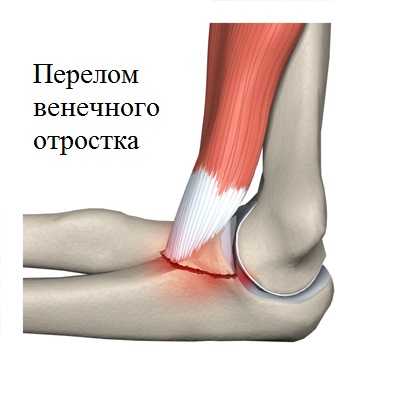

Венечный отросток играет большую роль в стабильности локтевого сустава. Травмы венечного отростка обычно сочетаются с повреждением связок.

При значительных переломах венечного отростка требуется операция поегорефиксации. Если операция по каким-либо причинам не выполнялась, возможно развитие нестабильности локтевого сустава, которая в будущем приведет к тяжелому артрозу. Репозиция и фиксация венечного отростка, а также восстановление связочного аппарата приводит к снижению риска подобных осложнений. Венечный отросток находится очень глубоко внутри сустава, возле него проходит множество важных нейро-сосудистых образований, в связи с чем открытая операция по его рефиксации требует большого разреза кожи и может быть чревата осложнениями. По этой причине операции под контролем артроскопа, будучи менее травматичными, имеют безусловное преимущество.

Во время операции при помощи артроскопа осматриваются все отделы локтевого сустава. Из сустава вначале удаляются сгустки крови, свободные внутрисуставные тела (мелкие костные фрагменты и небольшие кусочки хряща). Далее визуализируется непосредственно перелом венечного отростка. Напомним, что операция артроскопическим методом выполняется через два небольших прокола кожи. Изображение из полости локтевого сустава непосредственно с артроскопа передается на большие мониторы в операционной.

После репозиции, сопоставления костных отломков венечного отростка, с помощью специального направителя в область перелома вводится спица. Положение спицы контролируется рентгеном. В том случае, если положение спицы и перелома удовлетворительное, через разрез в 5-7 мм по спице проводится винт. Полученные в нашей клинике результаты лечения переломов венечного отростка подобным малоинвазивным способом оказались очень обнадеживающими. После операции локтевой сустав фиксируется ортезом на 2 недели. Пациенту разрешается постепенная разработка движений в суставе.

• венечного отростка возникает как следствие падения на согнутый локоть.

При переломе локтевого и венечного отростка без смещения накладывают гипсовую повязку сроком на 3-4 недели. При смещении фрагментов больше чем на 5мм при переломе локтевого отростка проводят оперативное вмешательство методом остеосинтеза (соединение костных отломков при помощи фиксирующих конструкций, которые обеспечивают неподвижность костных фрагментов). При вклинивании осколка в локтевой сустав при переломе венечного отростка оперативно удаляют этот фрагмент.